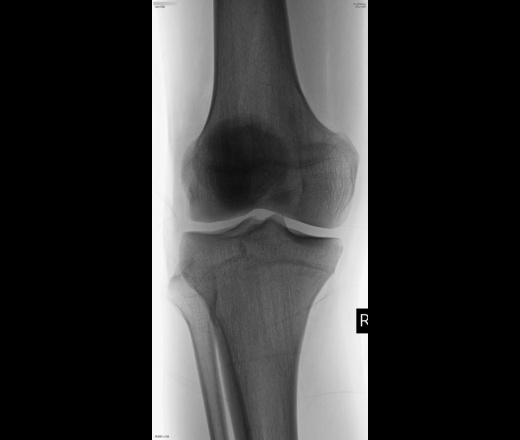

Молодой парень. Травму упоминает. Колено периодически выскакивает в сторону - так страдание описывает. По УЗИ повреждение медиального рога мениска врач заключает. А у меня на снимках - пара эностозов моргает?.. https://radiomed.ru/sites/default/files/styles/case_slider_image/public/user/19832/504_lst_0001.jpg?itok=HwVJ3zhU ID:45195 Сб, 13/09/2014 - 21:57 #1 алкс Не на сайте Был на сайте: 10 лет 5 месяцев назад Зарегистрирован: 24.10.2012 - 22:55 Публикации: 2915 И? Эностозы мениск рвут? Ср, 17/09/2014 - 21:27 #2 ЕЕЮ Не на сайте Был на сайте: 2 года 7 месяцев назад Зарегистрирован: 26.08.2013 - 11:22 Публикации: 410 Покажите где они?

Покажите где они?